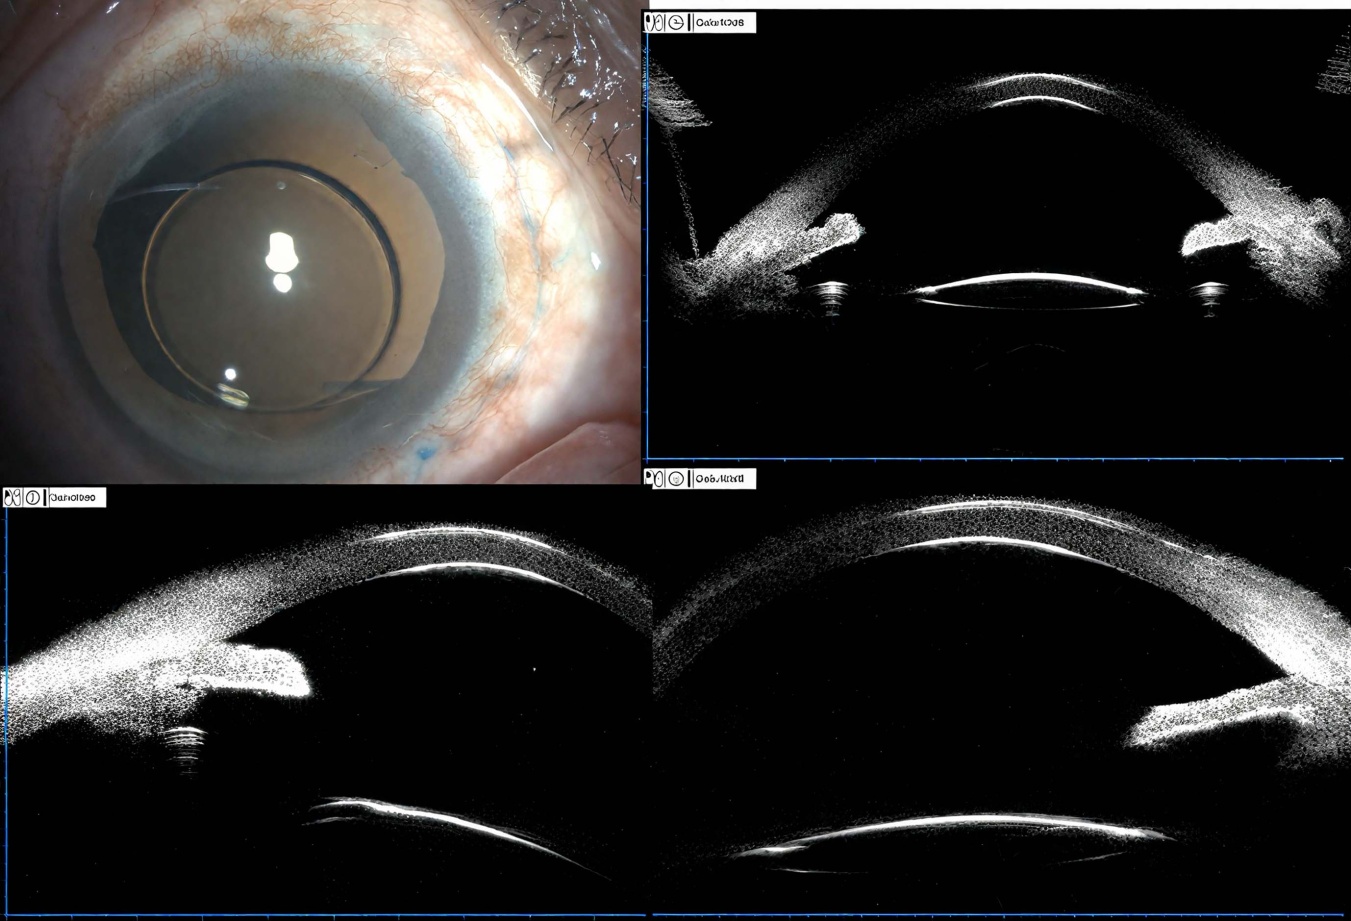

患者男,51岁,因“右眼被树枝干击伤后视物不见2天”就诊于青岛大学附属医院眼科门诊。既往无特殊眼病史。眼科检查:视力右眼HM/BE,左眼0.8;眼压右眼10 mmHg,左眼15 mmHg。右眼眼睑可见斜行裂伤,球结膜高度充血水肿,角膜轻度水肿,上方前房深度2 CT,下方前房几乎消失,房水细胞(+++),瞳孔欠圆,直径8 mm,对光反应迟钝,瞳孔区玻璃体疝入前房,晶体混浊并脱位于前房,晶体下方前表面与角膜内皮面相接触,眼内窥不清。超声生物显微镜(ultrasound biomicroscopy, UBM)检查示右眼自12点到6点睫状体与巩膜突间存在一无回声裂隙,睫状体上腔与前房相通(见图1)。左眼未见明显异常。诊断:右眼钝挫伤、睫状体离断、创伤性晶状体全脱位、外伤性麻痹性散瞳。入院后给予抗生素滴眼液预防感染,地塞米松10 mg∙qd静滴减轻炎症反应,于局麻下行右眼玻璃体切除联合白内障超声乳化摘除联合睫状体离断复位缝合术。术中先行白内障超声乳化摘除脱位晶状体。眼内探查见睫状体自12点到6点大范围离断,将8-0聚丙烯缝线尾端导入30G针内,自睫状体离断对侧9点方位角膜缘后3 mm进针,12点方位角膜缘后2 mm穿出,抽出线尾。穿刺针撤回眼内,间隔1个钟点位,再次穿出巩膜。眼外缝线尾穿过第二针线环。穿刺针撤回眼内,间隔1个钟点位,再次穿出巩膜,重复上述步骤,直至6点方位最后一次巩膜穿刺,将穿刺针内缝线拉出针管置于眼外,整理并拉紧缝线,将线头线尾在最后一个巩膜穿刺口附近打结(见图2)。于角膜缘后3 mm做三通道巩膜穿刺口,切除中央玻璃体,注入曲安奈德玻璃体染色,无玻璃体后脱离,人为制造后脱离,顶压下切除基底部玻璃体。术后给予糖皮质激素、抗生素滴眼液等点眼,进行抗炎抗感染治疗。术后第3天,右眼眼压为13.0 mmHg。术后1个月,右眼眼压17.0 mmHg,超声生物显微镜示睫状体复位良好,睫状体复位手术成功(见图3)。术后1个月,行二期人工晶体悬吊术,术后第3天,右眼裸眼视力0.25,1个月后,右眼加小孔矫正视力0.7。

Figure 1. Preoperative ultrasound biomicroscopy images

1. 术前超声生物显微镜图像